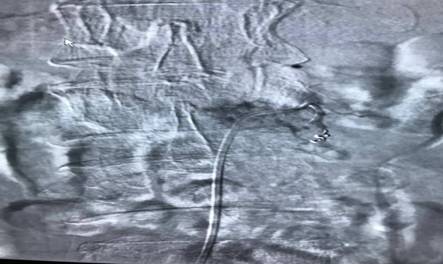

患者劉先生,54歲,患肝癌16個月,因腰腿痛伴下肢麻木4月余入住中心醫(yī)院脊柱外科。腰椎MRI顯示腰2椎體轉(zhuǎn)移腫瘤、椎管占位、神經(jīng)根受壓,PECT顯示腫瘤單節(jié)段椎體侵犯、椎弓根骨折。手術(shù)指針明顯。為最大限度地挽救患者的神經(jīng)功能,改善其生活質(zhì)量,脊柱外科決定為其施行手術(shù)切除減壓。術(shù)前,蘇光輝、汪向東二位主任帶領(lǐng)科室技術(shù)骨干與腫瘤科尹忠文主任、血管外科涂宏主任、麻醉科段雪琴主任多次會商術(shù)前計劃,經(jīng)周密術(shù)前準(zhǔn)備后,術(shù)前當(dāng)天由血管外科先行瘤體血管栓塞術(shù),以減少術(shù)中出血,栓塞手術(shù)非常成功,手術(shù)按時進行。術(shù)中蘇光輝主任、汪向東副主任與肖華斌、陳威副主任醫(yī)師為其施行腫瘤椎體全切術(shù)。術(shù)中出血量在2000ml以內(nèi),出血量的控制超出手術(shù)團隊的預(yù)期。手術(shù)相當(dāng)順利,術(shù)后患者快速康復(fù)出院。

脊柱腫瘤手術(shù)治療一直是脊椎外科的熱點難點,也頗具爭議,因其手術(shù)創(chuàng)傷大、解剖結(jié)構(gòu)復(fù)雜,特別是難以控制的大出血常常導(dǎo)致手術(shù)失敗,甚至危及患者生命。此次脊柱外科與腫瘤內(nèi)科、血管外科、麻醉科緊密合作。采取術(shù)前栓塞,術(shù)中控制性降壓,為脊柱全切術(shù)創(chuàng)造了良好條件,也為多科合作聯(lián)合開展高難度手取得了成功經(jīng)驗。

腫瘤血管栓塞前造影圖片

腫瘤血管栓塞后造影圖片